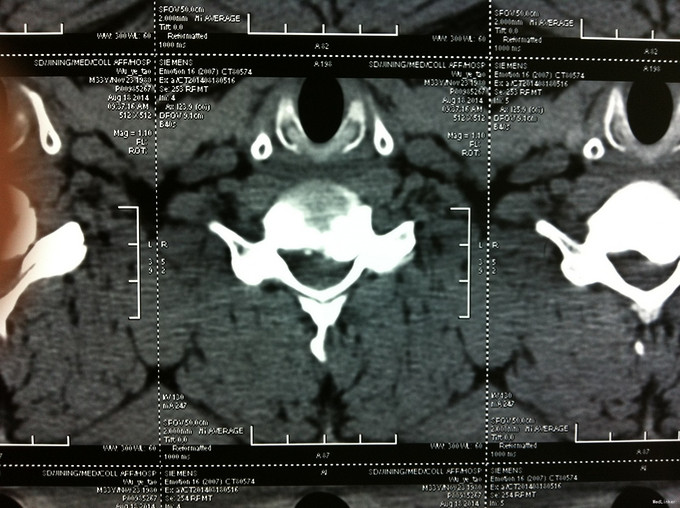

查体:左侧前臂及手感觉减退,右侧正常,左侧伸腕、伸肘肌肌力4级,右侧伸腕、伸肘肌肌肌力4-5级,双侧霍夫曼综合征阳性,双下肢肌张力高,膝腱反射+++,巴氏征阳性,辅助检查: X-ray:劲椎退行性变 CT及MR:颈椎间盘突出,腰5/6,6/7间盘突出并骨赘形成

诊断:脊髓型颈椎病 处理: 1、完善相关辅助检查,明确诊断,有无手术指证; 2、全麻下行颈椎前路减压,颈椎间盘突出并骨赘形成,行颈6椎体次全切,减压较充分。